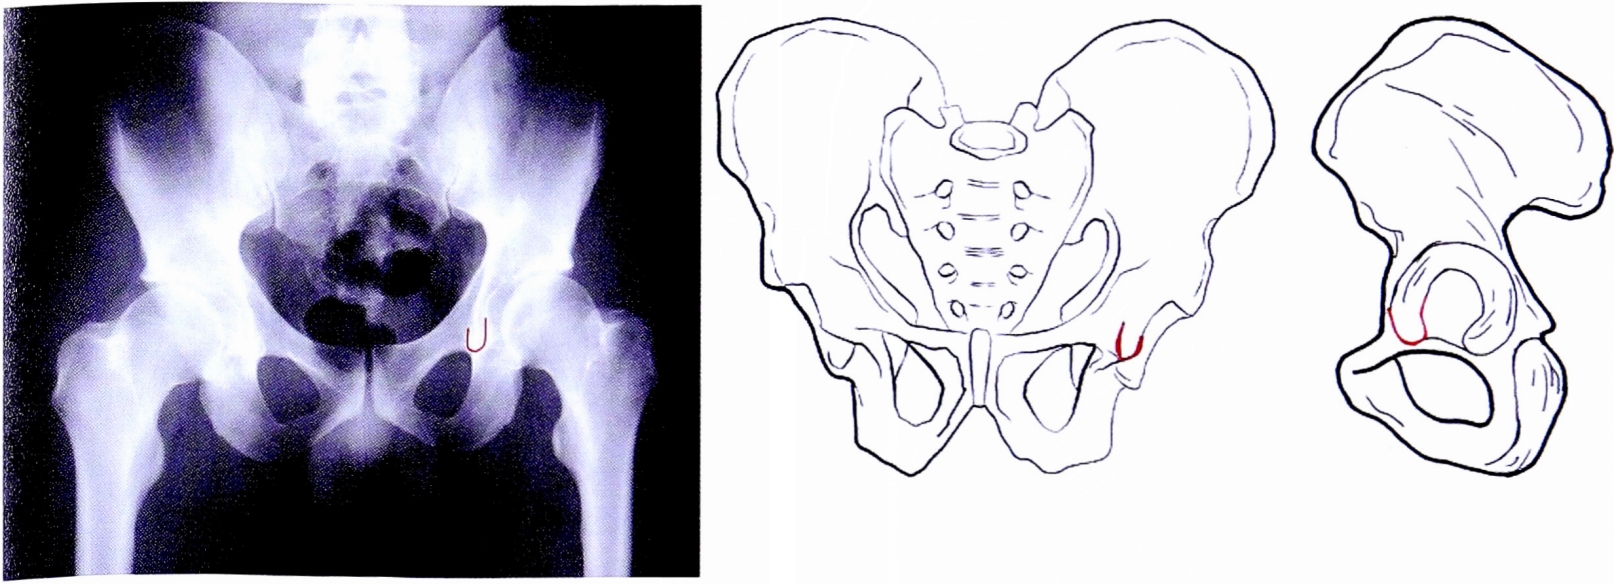

Рис. 4. «Фигура слезы» на рентгенограмме и на схематическом изображении таза.

Fig. 4. Teardrop line on AP pelvic X-ray and on schematic pelvis.

- Фигура слезы представляет собой передненижнюю часть суставной поверхности вертлужной впадины, имеющей подковообразную форму, соответвует медиальному отделу нижнего края суставной поверхности впадины. Является ориентиром для определения истинного положения дна вертлужной впадины (рис. 4).